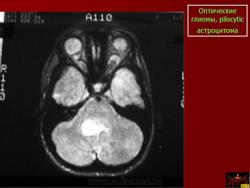

КТ и МРТ обеспечивают обнаружение точной локализации. Когда опухоль вовлекает в процесс оптический нерв, то это, обычно, грибовидное утолщение оптического нерва, которое иногда продолжается через оптический канал, вовлекая интракраниальную порцию до хиазмы [22]. Кроме того, глиомы могут проявляться в виде расширения и утолщения самого нерва по его длиннику [39]. Глиомы оптических путей обычно изоденсивные, у многих из них плотность увеличивается при введении контрастного вещества внутривенно [17]. При современных дополнительных методах исследования редко возникает необходимость в обычной рентгенографии черепа, которая классически демонстрирует изменения седла по вторичному типу в виде истончения контуров верхней части спинки и утолщения седла за счет увеличения сагиттального размера, оптические каналы имеют диаметр более 7 мм или разница между диаметрами обоих зрительных каналов более 2 мм [18].

В диагностический комплекс при опухолях зрительных путей, распространяющихся на гипоталамус, входят КТ [12, 17], МРТ головного мозга, иногда ПЭГ, КАГ, которые информативны лишь при опухолях больших размеров. Многие авторы не выделяют глиомы хиазмально-гипоталамической локализации от других локализаций, однако некоторые [19] свидетельствуют, что прогноз при таких опухолях весьма серьезен. В свете различия в дифференциальной диагностике и течении хиазмально-гипоталамических опухолей хирургический подход обсуждается многими аторами [1, 2, 9, 34, 36, 37, 44, 45].

Диагноз глиомы устанавливают на основании результатов компьютерной томографии, с помощью которой можно не только визуализировать увеличенный зрительный нерв в орбите, но и судить о распространении опухоли по каналу зрительного нерва в полость черепа (рис. 20.22). Ультразвуковое сканирование недостаточно информативно, так как представляет изображение только проксимальной и средней третей зрительного нерва. С учетом крайне медленного роста опухоли лечение строго индивидуально. При сохранении зрения и возможности наблюдения за больным альтернативой длительного наблюдения может быть лучевая терапия, после которой отмечается стабилизация опухолевого роста, а у 75 % больных — даже улучшение зрения. Хирургическое лечение показано при поражении опухолью только орбитального отрезка зрительного нерва в случаях быстро прогрессирующего снижения зрения. Вопрос о сохранении глаза решают до операции. Если опухоль прорастает до склерального кольца, что хорошо видно на компьютерных томограммах, пораженный зрительный нерв подлежит удалению вместе с глазом, и об этом следует обязательно предупредить родителей ребенка. В случае распространения опухоли в канал зрительного нерва или полость черепа вопрос о возможности выполнения оперативного вмешательства решает нейрохирург. Прогноз для зрения всегда плохой, а для жизни зависит от распространения опухоли в полость черепа. При вовлечении в опухолевый процесс хиазмы смертность достигает 20—55 %. Невринома (синонимы: леммома, шваннома, нейролеммома) составляет 1/3 от всех доброкачественных опухолей орбиты. Возраст больных к моменту операции от 15 до 70 лет. Женщины болеют несколько чаще. В орбите источником этой опухоли в большинстве случаев являются ци-лиарные нервы, надблоковый или надорбитальный, она может формироваться также из леммоцитов симпатических нервов, иннервирующих сосуды менингеальной оболочки зрительного нерва и ретинальной артерии. Одним из первых признаков опухоли могут быть локализованные боли в пораженной орбите, невоспалительный отек век (чаще верхнего), частичный птоз, диплопия. У 25 % больных прежде всего обращает на себя внимание экзофтальм, осевой или со смещением. Опухоль чаще располагается под верхней орбитальной стенкой в наружном хирургическом пространстве. Зона кожной анестезии позволяет предположить "заинтересованность" надблокового или надорбитального нерва. У 1/4 больных отмечается анестезия роговицы. Большая опухоль ограничивает подвижность глаза в сторону ее локализации. Изменения на глазном дне обнаруживают у 65—70 % больных, чаще констатируют отек диска зрительного нерва. При ультразвуковом сканировании удается визуализировать тень опухоли, отграниченную капсулой. На компьютерной томограмме видны не только тень опухоли, но и ее взаимоотношения со зрительным нервом.